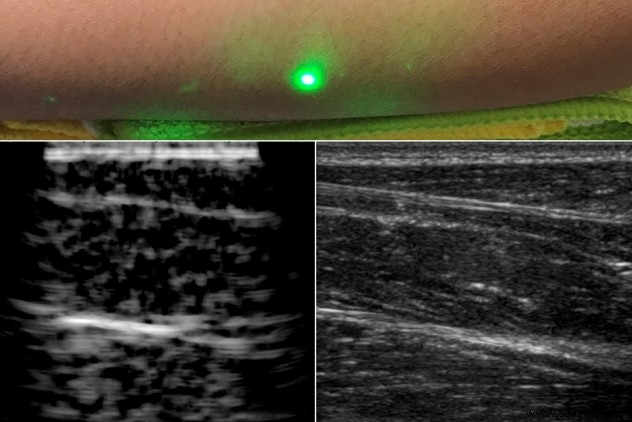

In a study published December 19, 2019, MIT senior research scientist Brian W. Anthony and his team introduced laser ultrasound. By using lasers to generate and detect waves remotely, this method eliminates physical contact entirely.

A pulsed laser at 1550 nanometers—safely absorbed by water in tissues—briefly heats the skin, creating expansion and ultrasound waves that travel through the body. A second continuous laser detects these waves via frequency shifts in reflected light, producing clear images.